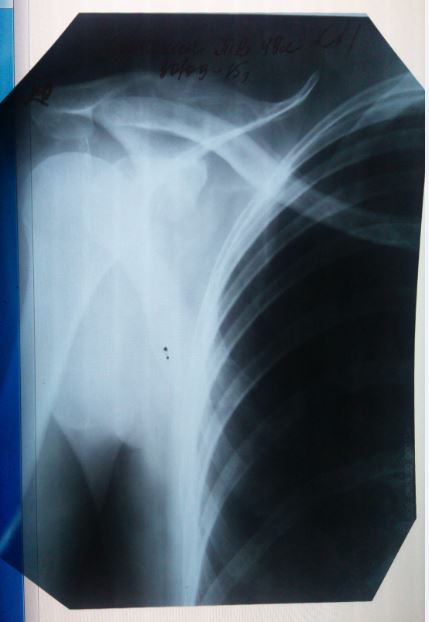

Здравствуйте,еще раз. Как сказала врач, в направлении там где написано " диагноз " - это то что показывают снимки.

Как еще врач говорит. По анализам все хорошо , по диаскинтест - отрицательно. Видимых симптомов нет , при осмотре-прослушивании тоже все хорошо. Как тогда может быть такой диагноз? Нет ни температуры.ни отдышки,ни головной боли,вес не теряла,не худела резко,в семье ни у кого такого не было.на учете не состояла. просто как так может быть что по снимкам развие " болезни " есть , а по анализам и тесту нет ?

Здравствуйте. Да, действительно случаи бывают разные. Тем и коварен уберкулез, что распознать его удается не всегда, и симптомов явным может не быть, и анализы могут не показывать всей картины. Но диагноз врач выставил на законных основаниях - изменения в легких типичны для туберкулеза. Консультируйтесь в областном центре, можно также сделать КТ (компьютерную томографию), ведь этот метод более точен, чем рентген.